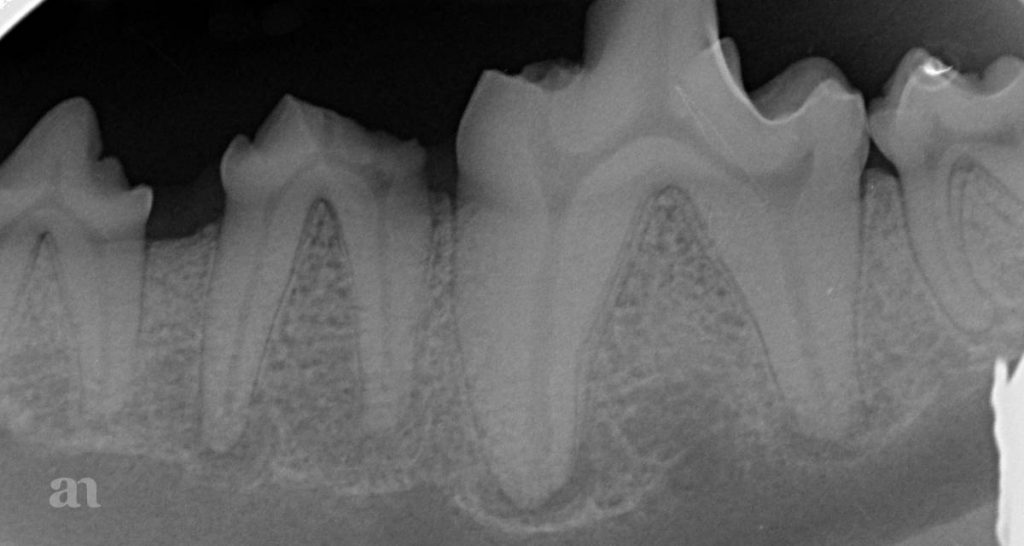

What Is Meant By Density On A Dental Radiograph . Dentists prescribe various radiographic examinations every day to complement their clinical evaluations so as to reach the most accurate diagnoses. • the difference in the degree of blackness (densities) between adjacent areas on a dental radiograph is known as contrast. Radiographic imaging is an integral part of the diagnostic process in clinical dentistry. The amount of darkness in the radiographic image reflects the radiographic density. In general, findings in dental radiographs are classified as radiolucent, radiopaque or mixed density, depending on their appearance when compared to the adjacent. Radiolucent (dark) air space, soft tissues, abscesses, tooth decay, and dental pulp appear as radiolucent images (dark). Milliamperage, as with kilovoltage peak, has an effect on the density of a dental radiograph. This article provides the fundamentals of radiographic interpretation beginning with. An increase in milliamperage increases the overall density of the radiograph and results in a darker. It is called transmitted density in.